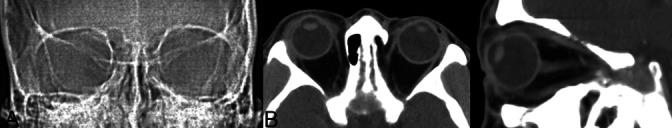

Twenty-six eyes of 26 patients were enrolled in the study. Fifteen patients (57.7%) had an intraocular foreign body (IOFB). The IOFB was metallic in 13 cases and glass and stone in the other 2 cases. Seven IOFBs (46.7%) were retained in the anterior chamber, 7 (46.7%) in the posterior segment, and 1 (6.7%) in the intraconal space. Univariate analysis showed that the presence of IOFB trended toward the development of endophthalmitis; however, this was not statistically significant (hazard ratio, 2.25; 95% confidence interval 0.35-14.61; P = 0.658). Eleven patients had metallic IOFBs noted on CT scans with metal artifacts, whereas two patients had small metallic IOFBs without metal artifacts. One patient had a glass IOFB mimicking metal artifacts on the CT scan. In one case, CT failed to reveal the IOFB, and an intralenticular metallic foreign body was incidentally found intraoperatively.

Our study provides a broad characterization of lawn trimmer-related open-globe injuries. The informative and diverse findings of IOFBs on CT scans will help clinicians detect and recognize IOFBs more precisely and perform the surgery without causing further damage.